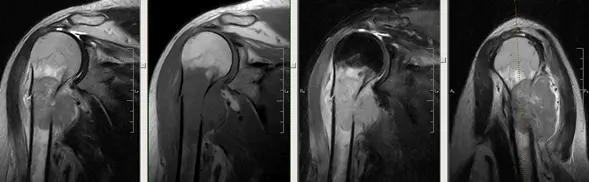

На зображенні: розрив сухожилля надостной м’язу.